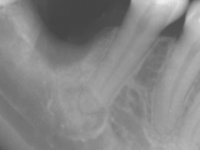

Paciente do sexo feminino, com 36 anos de idade, não fumadora. Apresentava o dente 1.1 com uma tonalidade mais escura que os dentes adjacentes. Feito o exame imagiológico, observou-se que o dente 1.1 tinha tratamento endodôntico, a paciente tinha 3 implantes colocados, dois no local dos dentes 1.2 e 2.2 e o outro no 4.6. A paciente tinha sido tratada ortodonticamente, apresentava um fenótipo gengival médio e uma boa higiene oral. Após 5 anos da primeira intervenção a paciente apresenta-se na consulta com sintomatologia infeciosa compatível com uma peri-implantite nos implantes 1.2 e 4.6. Após exame clínico, foi confirmada imagiológicamente. A perda óssea vertical tinha mais de 4mm nas duas situações.

Na primeira intervenção foi proposto à paciente uma coroa total com infraestrutura em Zr revestida por cerâmica. O facto do dente ter um tratamento endodôntico foi determinante nesta opção. Na segunda intervenção, foi proposto a remoção dos dois implantes. No implante colocado no local do dente1.2 seria feita uma regeneração óssea simultânea à colocação do novo implante. Contando com a inevitável retração gengival na zona cervical da coroa do 1.1, foi também proposto refazer a coroa do dente 1.1. Foi também adiantado que por questões de simetria, se fosse necessário, também poderia ter que se intervir no dente 2.2. Assim, na zona antero-superior, teríamos coroa aparafusada sobre um novo implante colocado no 1.2, nova coroa no1.1 e uma faceta ou coroa no dente 2.1 se necessário. No implante colocado na zona do 4.6, propomos removê-lo, colocar um novo implante, posteriormente reabilitado com uma coroa aparafusada.